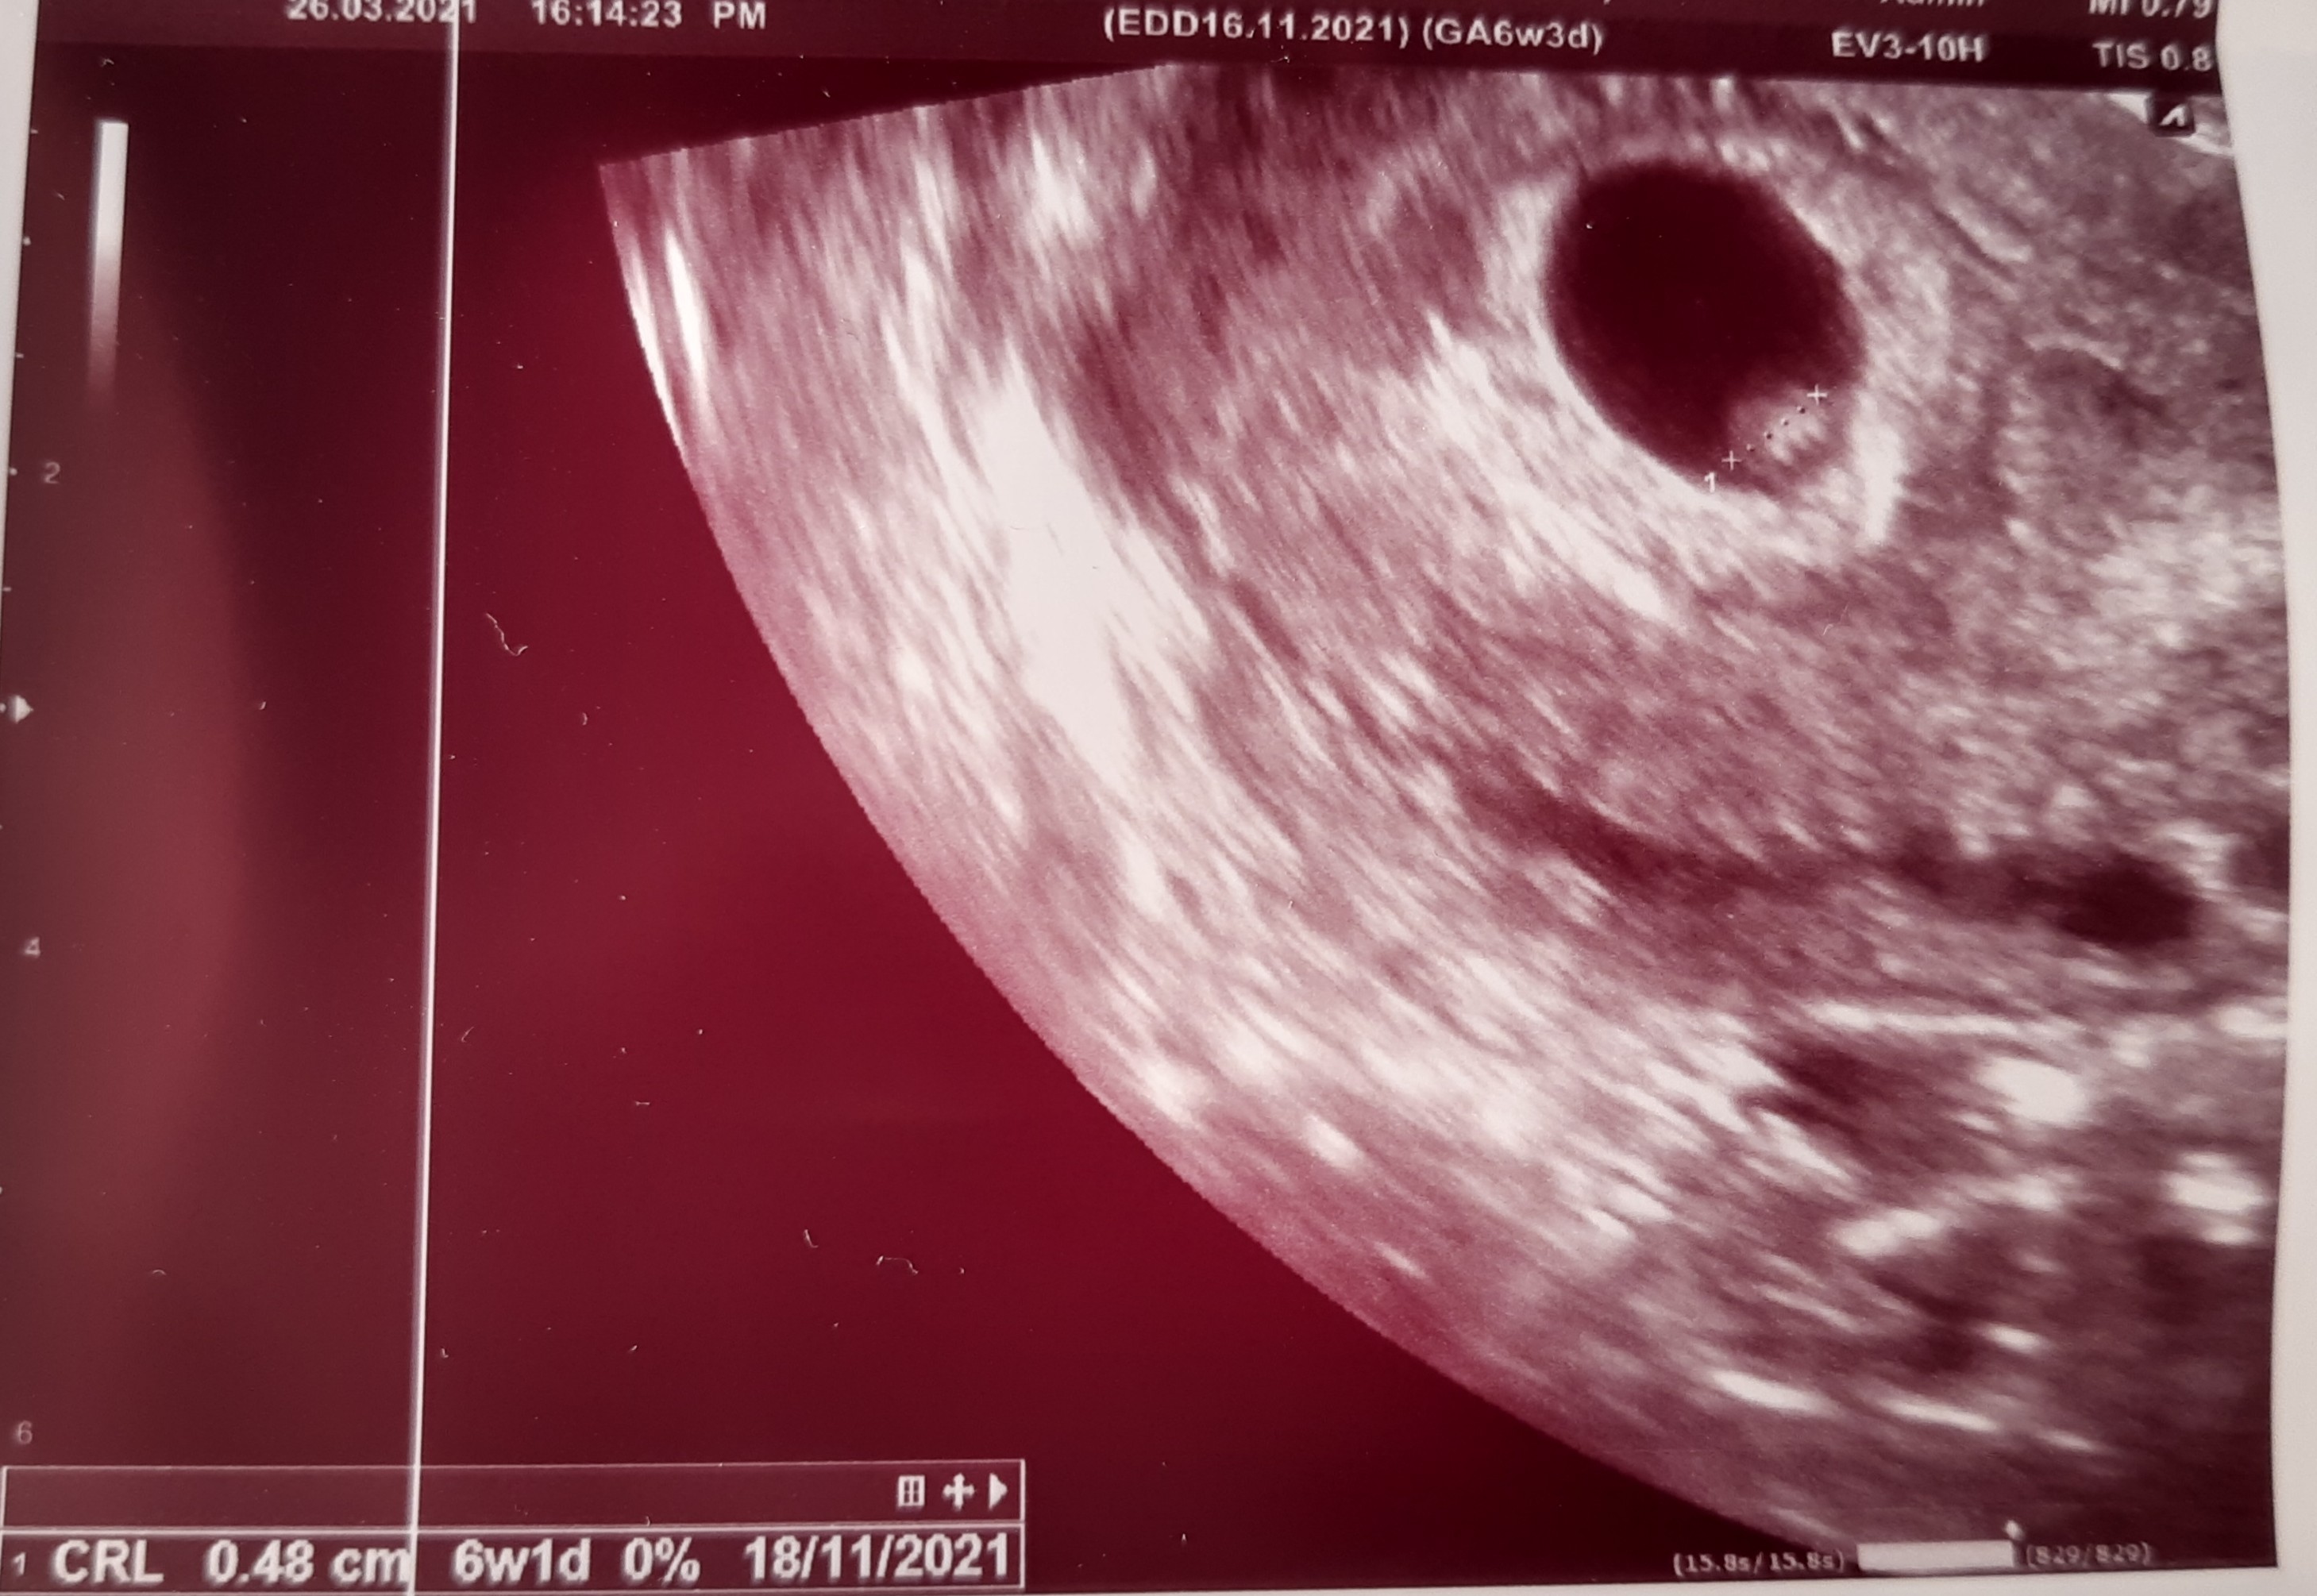

Zobacz załącznik 1252782

Jedno jajo,n ie puste z serduszkiem :)

Piękne, gratuluje! Moja ginekolog mi mówiła, że taki okrągły pęcherzyk ciążowy to bardzo dobry znak 😊